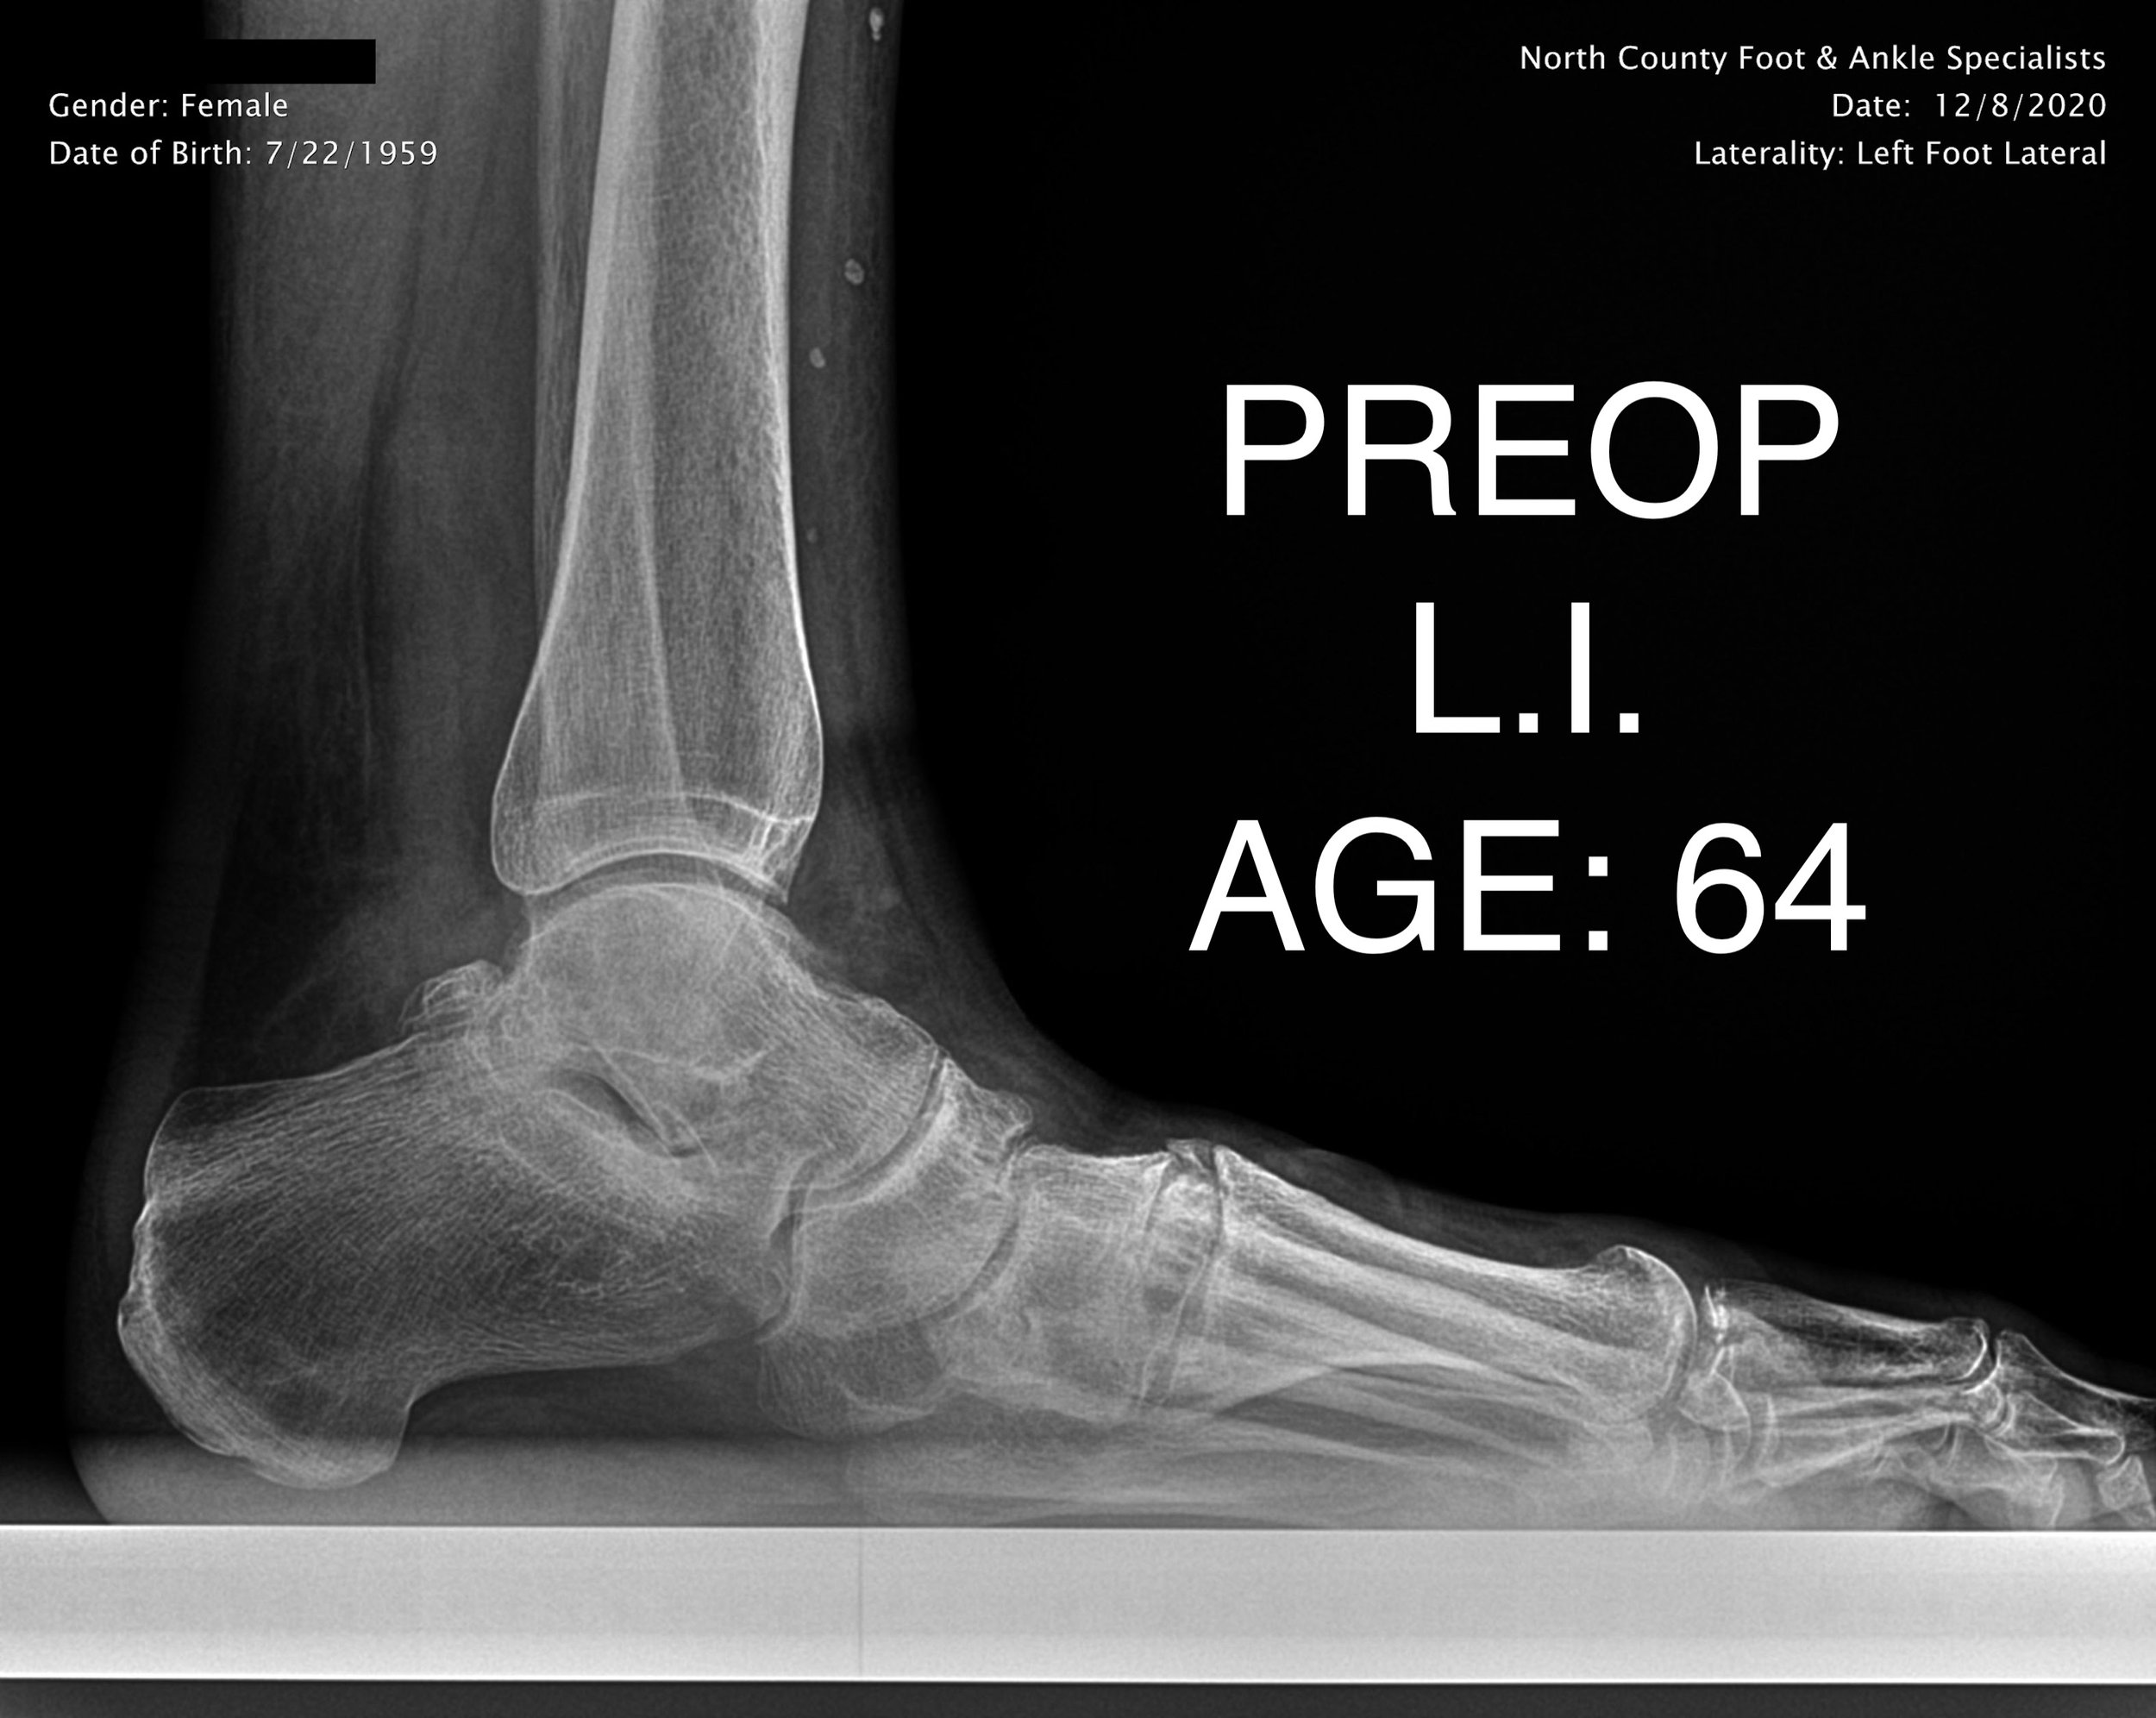

ADULT FLAT FOOT RECON